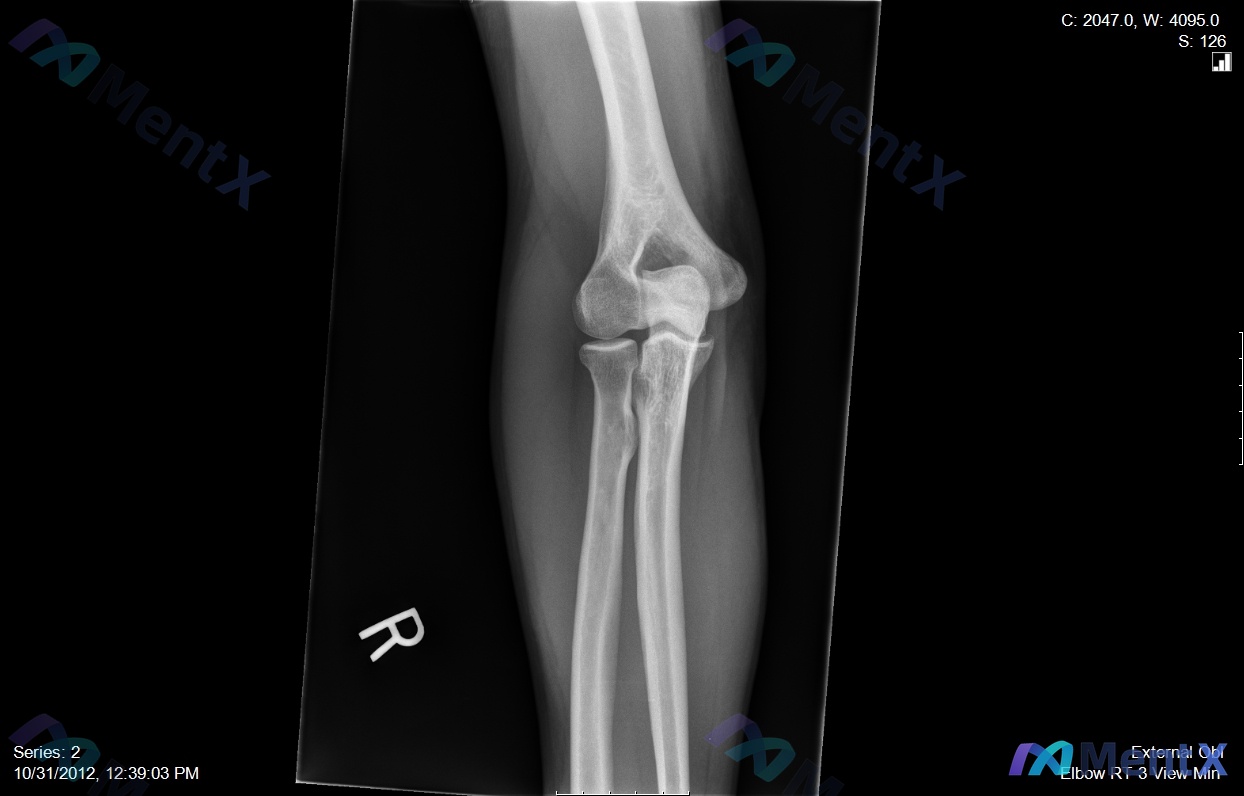

整理了一个挺有警示意义的病例,核心是「别被带偏,抓死核心体征」—— --- 病例基本情况 - 患者:35岁男性木匠 - 主诉:右肘前窝疼痛,用螺丝刀时明显加重 - 病程:6个月+,规范保守治疗(休息、抗炎、理疗)无效 关键体格检查 这个是破局核心: ✅ 钩试验(针对桡神经浅支卡压)正常 ❌ 但抗旋后...